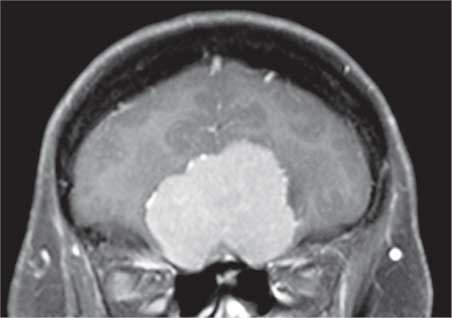

И это на самом деле так. Все повреждения передней части черепа могут нарушить их функционирование. На рисунке 36 можно видеть, как большая менингиома, доброкачественная опухоль, растущая из ткани, окружающей мозг, захватывает его именно в том месте, где обонятельные нервы проникают в череп. Естественно, что аносмия является обычным симптомом при заболеваниях подобного рода.

Иллюстрация к книге — Удивительные истории о мозге, или рекорды памяти коноплянки [i_035.jpg]

Рис. 36. Большая светло-серая масса, расположенная над носовыми полостями, это менингиома; в результате ее разрастания нарушается функционирование обонятельных нервов в том месте, где они проникают в череп